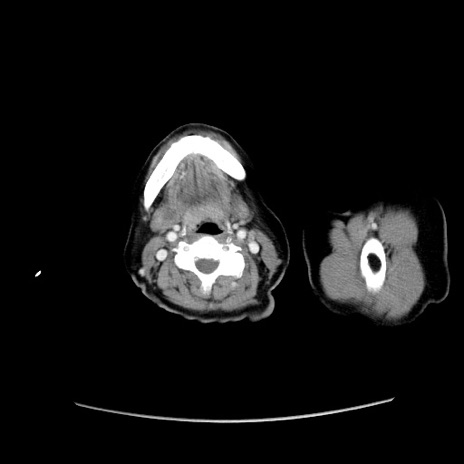

症例19(横断像)

【症例】80歳代女性

【主訴】下腹部痛

【現病歴】約8時間前より下腹部痛の出現あり、救急外来受診。

【既往歴】両側付属器切除

【身体所見】意識清明、下腹部正中に手術痕あり、その部位に一致して圧痛と反跳痛あり。腸蠕動音は亢進。

【データ】WBC 9300、CRP 0.15